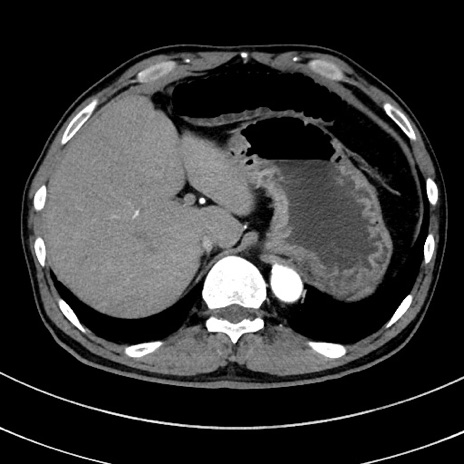

冠状断像

【症例】 60歳代男性

【主訴】 黒色吐物

【現病歴】 4日前から嘔気自覚、2日前の朝食後にも嘔気あり、自分で手で嘔吐反射起こし嘔吐したところ血が混ざっていたため受診。

【既往歴】 5年前汎発性腹膜炎を伴う急性虫垂炎で手術、高血圧、前立腺肥大症、高脂血症

【身体所見】 腹部正中に手術癩痕あり 腹部平坦・軟圧痛なし膨満感あり

【データ】WBC 8400、CRP 4.54